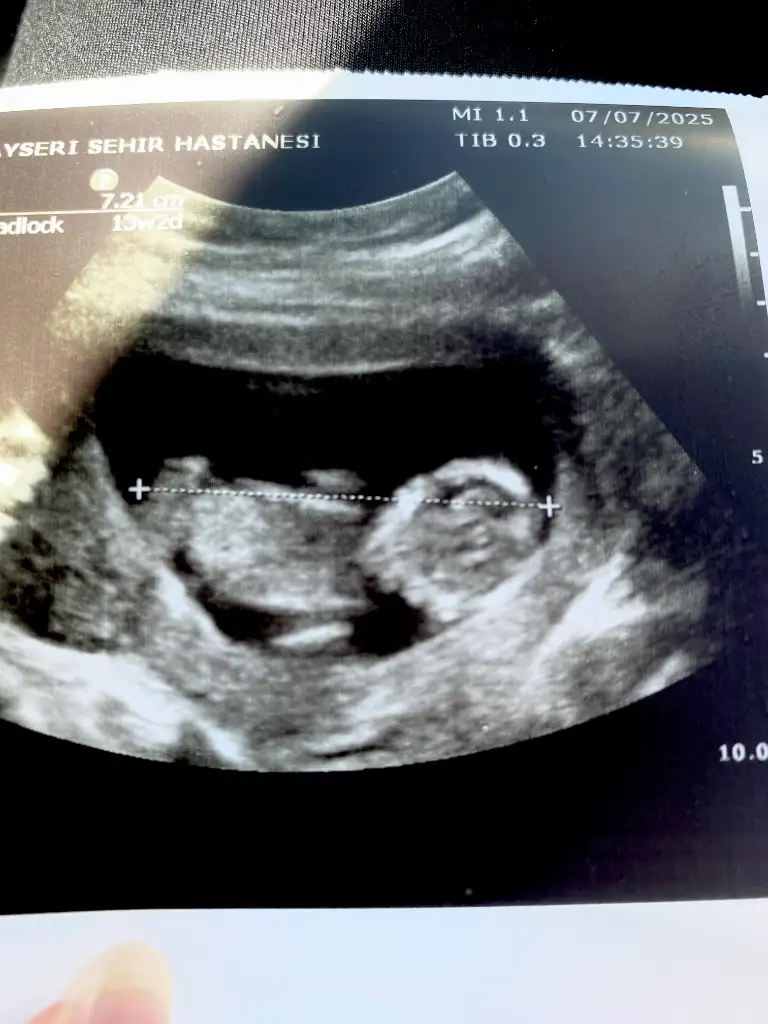

bunlarda benim torunlarım 13 haftalık ,

doktor erkek demiş , ama yanılma olurmu anlayan var mı